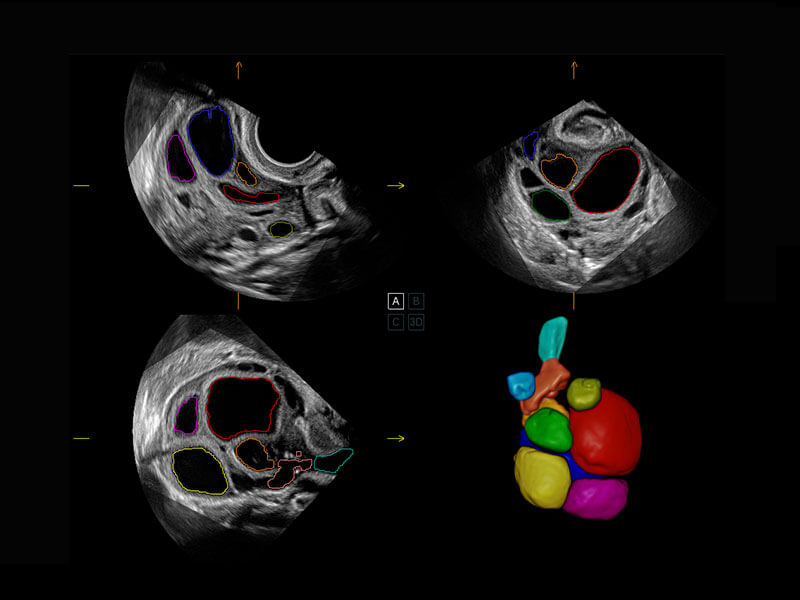

新生儿心脏

P60搭载一系列胎儿心脏成像技术,实现精细的胎儿心脏评估。

四腔切面

四腔心血流

右室双出口

胎心容积成像